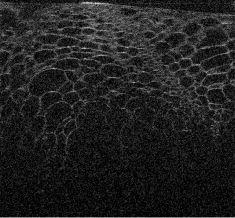

Visualizations of cross sectional reconstructions from the sub-sampled measurements are shown in Figure 2 and Figure 3 for the beaded gel and cucumber tissue samples respectively. Quantitative results of the NCC are then shown in Table 1.

From Figure 2, it appears that enhancement of the image structure is improved in each instance of MBIR. Random sub-sampling results in the best preservation of structure, followed by equispaced, and finally partial, which exhibits strong artifacts in each case. TV regularization appears to reasonably robust, but exhibits some block-like image artifacts, whilst DT-CWT has better preservation of speckle structure.

The cucumber tissues results in Figure 3 follow a similar trend to the beaded phantom, with very good preservation of structure for random and equispaced sub-sampling for both MBIR techniques. Again, partial measurements are significantly worse, with most of the structure degraded in the interpolated ISAM image.